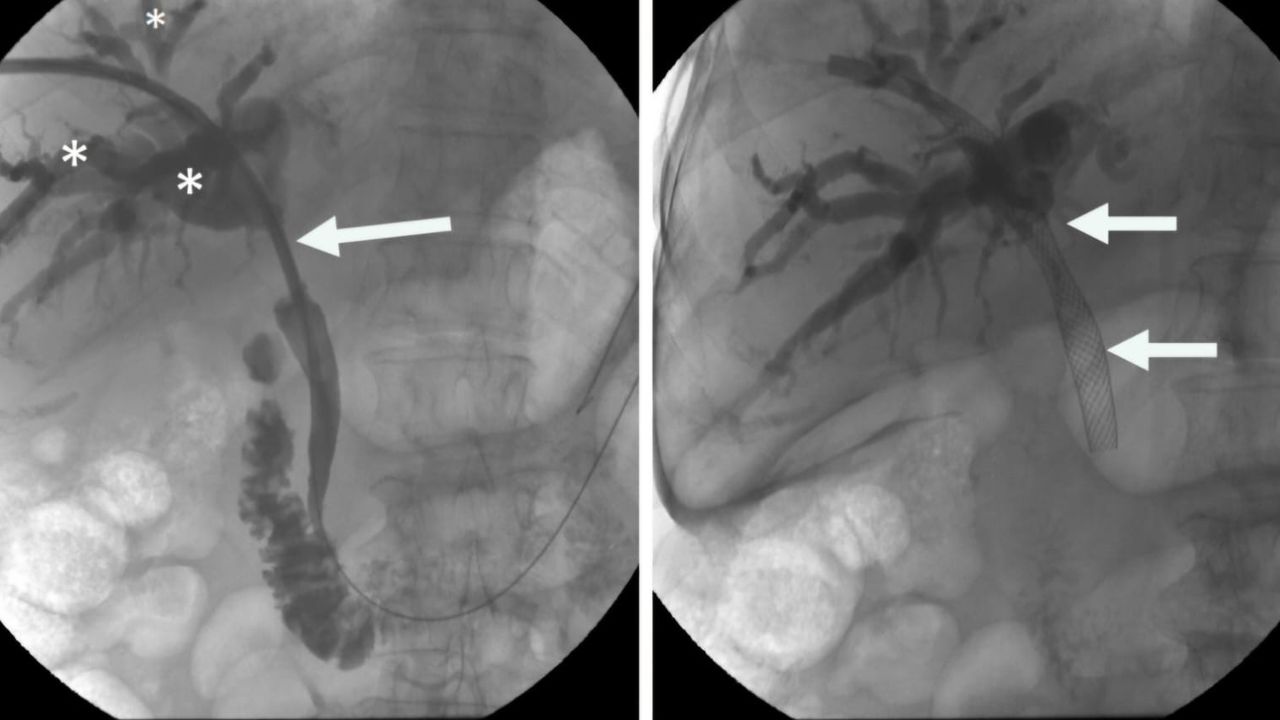

Prof. Dr. Ahmet Memiş'in önderliğinde uygulanan bu yenilikçi yöntem, endoskopik teknikleri ve iğne ile giriş yöntemlerini tek bir operasyonda birleştiriyor. Bu sayede, daha önce tedavisi çok zorlu kabul edilen karmaşık safra yolu problemleri artık daha etkili ve minimal invaziv bir şekilde tedavi edilebiliyor. Hibrit yaklaşımların en önemli avantajlarından biri, hastaların bedenine minimum düzeyde zarar vermesidir. Büyük cerrahi kesilerin yerine, endoskopik, gastro ve girişimsel radyoloji yöntemler kullanılarak, iğne deliği kadar küçük girişimlerle operasyonlar gerçekleştiriliyor. Bu da hastaların ameliyat sonrası ağrılarını azaltıyor, enfeksiyon riskini düşürüyor ve hastanede kalış sürelerini kısaltıyor.

Prof. Dr. Ahmet Memiş, “Hibrit yaklaşım, sadece tedavi değil, aynı zamanda tanı sürecinde de önemli avantajlar sunuyor. Hekim, hastanın vücuduna dokunmadan, radyolojik görüntüleme teknikleriyle hastalıklar daha hızlı ve doğru bir şekilde tespit ediliyor. Bu da tedavi sürecinin daha etkin bir şekilde planlanmasına imkan sağlıyor. Farklı disiplinlerden uzman hekimlerin bir araya gelerek oluşturduğu sinerji, karmaşık safra yolu sorunlarında başarı oranını önemli ölçüde artırıyor. Bu sayede, hastalar daha hızlı iyileşme göstererek günlük yaşamlarına daha kısa sürede dönebiliyor. Geleneksel cerrahi yöntemlerde uzun iyileşme süreleri ve yoğun ağrılar yaşanırken, minimal invaziv yaklaşımlar sayesinde bu sorunlar ortadan kalkıyor. Hastalar, operasyon sonrası çok daha kısa sürede taburcu oluyor ve gündelik aktivitelerine hızla dönebiliyorlar. Bu da hem hasta konforunu artırıyor hem de sağlık sisteminin üzerindeki yükü hafifletiyor” dedi.